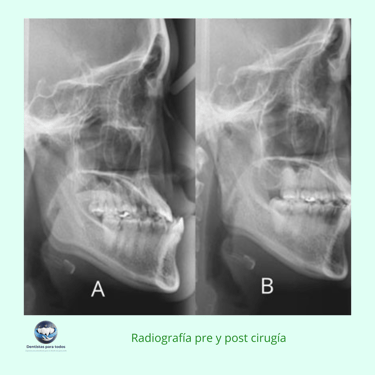

Evaluación Inicial: Examen clínico, radiografías y planificación quirúrgica detallada.

Resultados esperados: Corrección de la alineación maxilofacial, mejorando tanto la función masticatoria como la estética facial del paciente.